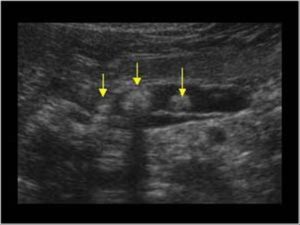

На представленной ниже фотографии отображена рентгенограмма (фото А) и томограмма брюшной полости больного, страдающего хроническим кальцифирующим панкреатитом, поступившим в хирургическое отделение после 72 часов острого болевого синдрома в эпигастральной области, с тошнотой и рвотой. Лабораторные исследования показали повышенный уровень в сыворотке крови липазы (173 U на литр), что указывает на диагноз панкреатит. Больной не употребляет алкоголь, а предыдущими исследованиями других причин развития панкреатита установлено не было.

Стрелками на рентгенограмме и на изображении, полученном при компьютерной томографии, указаны плотные кальцифицированные образования в поджелудочной железе.

Клиническая картина свидетельствует об обструкции главного панкреатического протока камнями, что типично для хронического кальцифицирующего панкреатита.